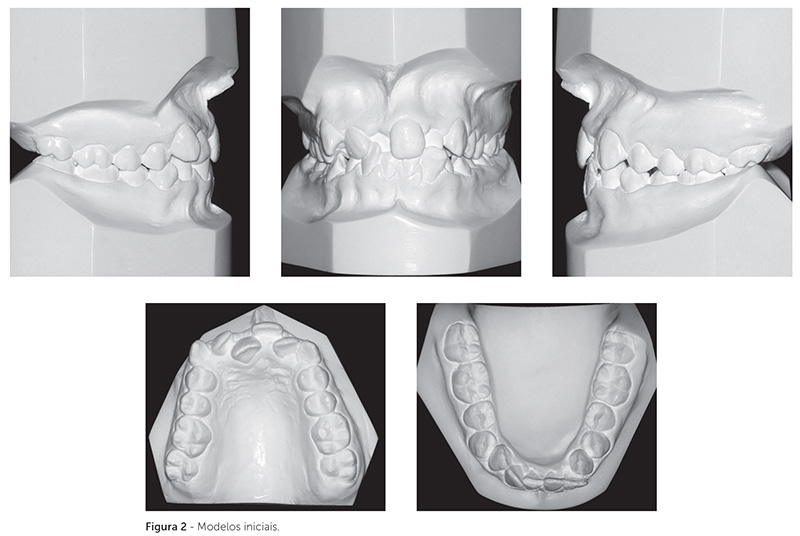

Do ponto de vista dentário, possuía má oclusão de Classe I de Angle (Fig. 1 e 2), embora os caninos superiores e inferiores estivessem em relação de topo no sentido anteroposterior. Havia apinhamento severo nas arcadas superior e inferior (discrepância superior de -10mm e inferior de -6mm) e mordida cruzada anterior dentária envolvendo os dentes 11 e 22. A sobressaliência entre os dentes 21 e 31 era de 3mm positivos, e entre os dentes 11 e 41 era de 3mm negativos. O dente 41 se apresentava fraturado e parcialmente restaurado, pois, em função da má oclusão, não havia espaço suficiente para realizar adequadamente a restauração, que fraturava constantemente. A higiene bucal era satisfatória.

Nas radiografias panorâmica e periapicais dos incisivos (Fig. 3), foi possível observar boa formação radicular de todos os dentes, ausência de rarefação apical no dente 41 fraturado e ausência de anomalias ósseas ou dentárias. Os terceiros molares estavam inclusos e no estágio 6 de Nolla, estando em fase inicial de formação radicular.